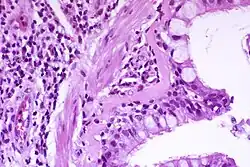

![]() væv med astma | |